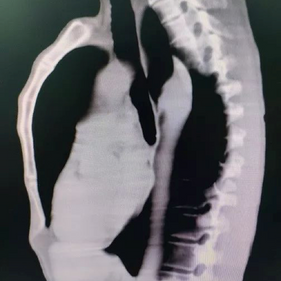

The patient is a 56-year-old male who has had a protruding chest wall since childhood, with the deformity becoming more pronounced after puberty. Since he experienced no discomfort, he didn’t seek treatment. However, as he aged, he became increasingly dissatisfied with the appearance of his chest wall and felt immense psychological distress, leading him to seek surgical treatment.

The patient was diagnosed with severe pectus carinatum. Initially, the Wenlin procedure was performed to correct the protrusion. Two 4 cm incisions were made on each side of the chest wall, and three shaped bars were placed on the protruding bone structure. By pressing down on the protruding chest wall and continuously adjusting the curvature of the bars, the deformed chest wall was gradually restored to its normal contour. Lastly, the Wang technique was performed, which features a special bar fixation method that utilizes steel wires instead of short fixation bars to secure the ends of the shaping bars. This is the primary distinction between the Wenlin procedure and the Nuss procedure or the Abramson procedure. As a result, the bars were secured directly to the ribs on both sides of the chest wall.

Since the anterior chest wall is a rigid whole, manually pressing down the protrusion in the upper chest often causes a secondary depression below it. The Wung procedure was performed to correct this depression. To avoid damaging the heart when directly inserting the bar, a passage tunnel was carefully constructed by manual exploration, and the fourth bar was slowly placed into the chest cavity. The bar was used to elevate the depression, and its ends were secured using the Wang technique. After the surgery, the patient’s protruding deformity disappeared, and the chest wall appearance was restored to normal.